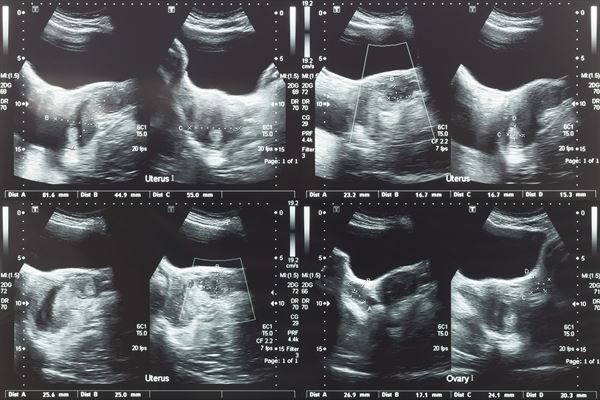

Badania USG są wykorzystywane w różnych obszarach medycyny, ponieważ pozwalają uzyskać dokładny obraz struktur wewnętrznych. Metoda ta nie wiąże się z bólem ani promieniowaniem rentgenowskim, co sprawia, że może być stosowana u szerokiej grupy pacjentów, w tym u kobiet w ciąży. Badania ultrasonograficzne odgrywają istotną rolę w wykrywaniu schorzeń na wczesnym etapie i umożliwiają monitorowanie postępu leczenia.

W gabinecie wykonywane są między innymi USG jamy brzusznej, pomocne w diagnostyce:

• chorób wątroby,

• chorób trzustki,

• chorób nerek,

• chorób pęcherzyka żółciowego.

USG tarczycy z kolei pozwala na ocenę wielkości i struktury gruczołu, a także wykrywanie guzków lub innych nieprawidłowości. W przypadku problemów z układem mięśniowo-szkieletowym wykonywane są badania USG stawów, mięśni, ścięgien i więzadeł, umożliwiające lokalizację stanów zapalnych, uszkodzeń czy zmian pourazowych. Lekarz przeprowadza też USG piersi, płuc i węzłów chłonnych oraz specjalistyczne badania Dopplerowskie tętnic szyjnych oraz żył kończyn dolnych.